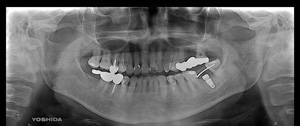

@@R.S‚³‚ñ@56Î —«  ‘åŠw‹³Žö @Žèp“ú@‚Q‚O‚O‚W”N ‚QŒŽ ‚X“úi“yj@㉺Š{  ƒm[ƒxƒ‹ƒKƒCƒhŽg—p@Ö¬“à’ÁÖ@•¹—p@@@

@@@@@ãŠ{  All on ‚U@‘¦Žž‰Ád@@

@@@@@@@@@@@@@ Rpl Tapered Rp  ‚P‚O mm(‚U–{)

@@@@@‰ºŠ{¶‰E@‘¦Žž‰Ád@ ‚R Unit Bridge@

@@@@@@@@@@@ @Rpl Tapered Rp  ‚P‚O mm(‚S–{)@@–ƒWƒ‹ƒRƒjƒAƒNƒ‰ƒEƒ“‚ÅÅI•â’Ô